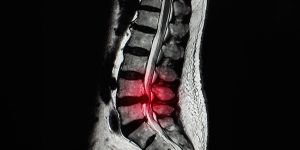

La hernia discal ocurre cuando el material del disco intervertebral presiona los nervios cercanos. El Dr. Valle alivia el dolor y recupera la movilidad mediante tratamientos avanzados.

Es el estrechamiento del canal vertebral que comprime la médula espinal o los nervios. El doctor ofrece soluciones efectivas para reducir la presión y mejorar la calidad de vida.